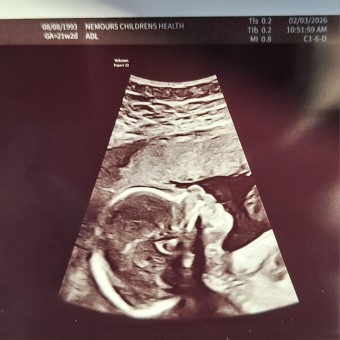

Baby Sebastian 💙

Jessica Haake & Style Coatney

June 14, 2026